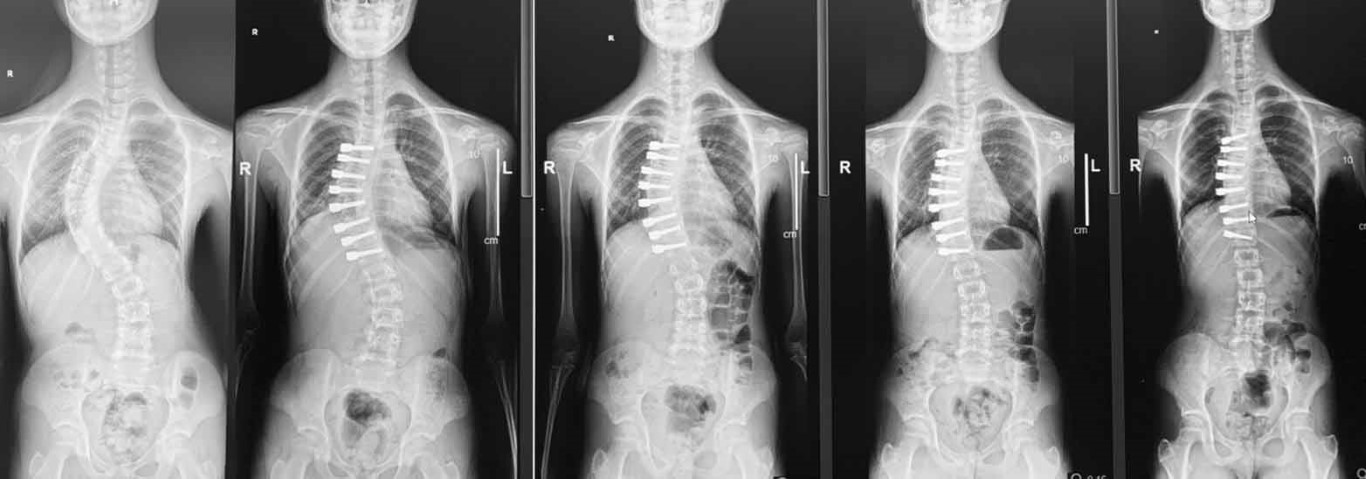

Ortopedi ve Travmatoloji Uzmanı Doç. Dr. Tuna Pehlivanoğlu, skolyoz hastası çocukların tedavisi hakkında konuştu. Genelde çocuklarda skolyoz hastalığının görüldüğünü belirten Pehlivanoğlu, 40 derecenin üzerindeki eğriliklere ameliyatla tedavi önerildiğini söyledi. Klasik skolyoz ameliyatında omurgaya arkadan yerleştirilen vidalar nedeniyle çocukların omurgalarında hareket engelinin meydana geldiğini ifade eden Pehlivanoğlu, tedavinin sonucunda çocukların büyüme ve gelişmelerinin durduğunu kaydetti. Ancak geliştirilen ipli ameliyat yöntemiyle skolyoz hastası çocukların büyüyüp gelişebileceğini belirten Dr. Pehlivanoğlu, ameliyatı uyguladıkları profesyonel sporcuların ve dansçıların da olduğunu aktardı. Ameliyat yöntemi hakkında bilgi veren Doç. Dr. Tuna Pehlivanoğlu, göğüs boşluğunun kenarından küçük kesik yaparak vidaların kamera yardımıyla koyulduğunu ardından da araya bir ip gerilerek skolyozu düzelttiklerini anlattı. Bu yöntemi göğüs boşluğunun iki tarafından da vida yerleştirerek uygulanabilir hale getirdiklerini söyleyen Pehlivanoğlu, eğriliği fazla olan çocuklara vidaların bir kısmının sağdan bir kısmının ise soldan yerleştirildiğini belirtti. Öte yandan tedavinin büyüme potansiyeli olan, büyümesi devam eden, eğriliği esnek olan ve genelde 60-65 dereceyi geçmeyen hastalara uygulandığını da aktardı.

Ameliyat yöntemini uygulamada dünyadaki öncülerden bir tanesi olduklarını ifade eden Pehlivanoğlu, "Burada yaptığımız iş klasik ameliyattaki gibi sırttan büyük bir kesik yapmak değil. Göğüs boşluğuna kenardan ufak kesik yaparak vidaları kamera yardımıyla koyuyoruz. Araya da bir ip gerdiriyoruz. Gerdirmeyle eğriliği yani skolyozu düzeltiyoruz. Sonrasında çocuk büyüyerek kendi kendisini de düzeltiyor. Bu ameliyat eskiden tek bir taraftan yapılabiliyordu. Vidalar tek bir taraftan koyulabiliyordu. Biz bunu iki taraftan da yapılabilir hale getirdik. Yani eğriliği daha fazla olan çocuklarda vidaların bir kısmını sağ taraftan, bir kısmını da sol taraftan koyuyoruz. Bu şekilde düzeltiyoruz. Eskiden ipli skolyozla bunu yapmak mümkün değildi. Biz dünyada ilk olarak bunu uygulayıp literatürde de yayınlayarak mümkün olduğunu gösterdik. Artık o çocuklarda ipli skolyozla tedavi olabiliyorlar. İpli skolyoz herkese uygulanmaz. İpli skolyozu uygulayabileceğimiz hastalar, büyüme potansiyeli olan, büyümesi devam eden, eğriliği esnek olan ve genelde 60-65 dereceyi geçmeyen hastalara uyguluyoruz" şeklinde konuştu.